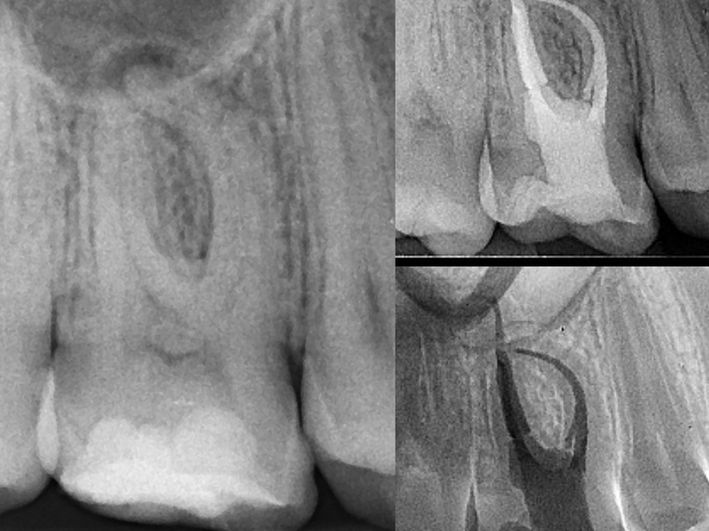

4. Tratament ortodontic pacient adult

O perioadă a existat preconcepția că tratamentul ortodontic este destinat doar copiilor sau adolescenților. Acest lucru nu este adevărat, putând fi realizat la orice vârstă. Particularitatea tratamentelor la pacienții adulți vine din prezența celorlalte patologii dentare și necesitatea colaborării cu celelalte discipline (chirurgie, parodontologie, endodonție, protetică).

În acest caz am realizat retratament endodontic 2.6, extracție 4.6, tratament ortodontic, inserare implanturi în locul dinților lipsă 1.6, 3.6, 4.6, coroane dentare din zirconiu multilayer înșurubate pe implanturi.